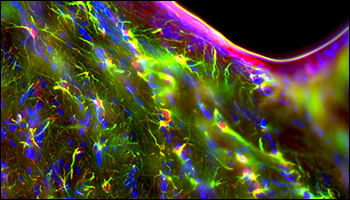

Monochrome TIF Images (Shown with False Color):

DAPI (405 nm)

GFAP (488 nm)

s100B (555 nm)

Three-channel immunofluorescence image of a mouse brain acquired using the CS895MU Camera.

(Sample prepared by Lynne Holtzclaw of the NICDH Microscopy and Imaging Core Facility, NIH, Bethesda, MD)

こちらからフル解像度画像がご覧いただけます。

カメラCS895MUで取得したマウス脳の3チャンネル免疫蛍光画像。

試料ご提供:Lynne Holtzclaw of the NICDH Microscopy and Imaging Core Facility, NIH, Bethesda, MD.